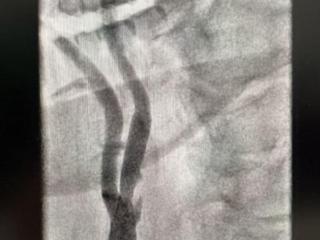

技术突破!青岛西海岸第二院脑血管病科成功开展山东省内首例 “应用IVUS指导下精准颈动脉狭窄介入治疗”